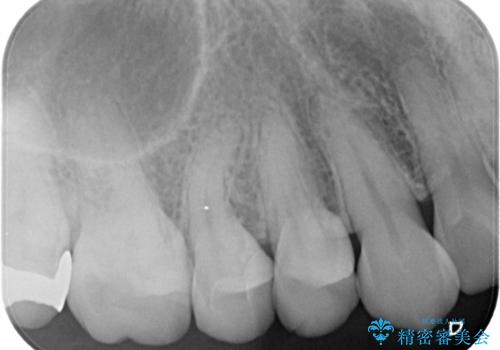

【セラミックインレー】昔治療した詰め物が外れた。

- 他院でいれたセラミックインレーが脱離して、来院されました。

新たに製作を希望されたため、当院で治療しました。

当院でのセラミックインレーの治療は、ラバーダムを使用しています。